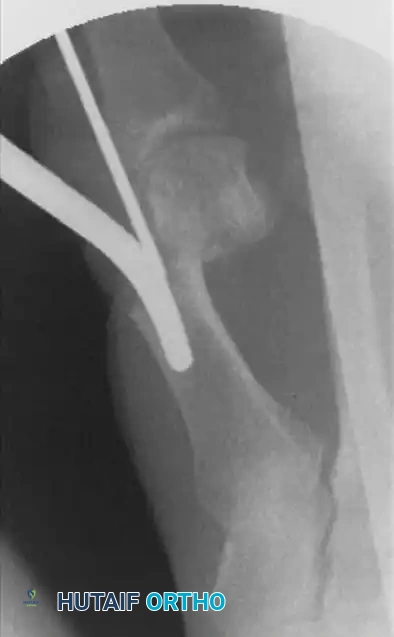

إدخال سلك التثبيت الدقيق

الخطوة الأولى تتمثل في وضع السلك المعدني الدقيق الذي سيقوم لاحقا بالتقاط وتثبيت رأس العظمة بعد قصها. يتم إدخال سلك بقطر ملليمترين بدءا من الزاوية الداخلية لظفر إصبع القدم الأكبر.

إدخال السلك المعدني الدقيق

يحرص الجراح بشدة على تجنب اختراق منبت الظفر لتفادي أي ألم أو تشوه في الظفر بعد الجراحة. يتم دفع السلك نحو الأعلى بحذر شديد. من الضروري جدا أن يمر السلك في مسار خارج غشاء العظم على طول الجانب الداخلي للإصبع. هذا المسار الدقيق هو ما يسمح لاحقا بإزاحة العظم وتصحيح التشوه.

مسار السلك المعدني خارج غشاء العظم

يتم دفع السلك حتى يستقر بقوة في الجانب الداخلي لرأس عظمة المشط. هذا التثبيت المحكم ضروري لمنع العظمة من التحرك بعشوائية بعد قصها.

بمجرد الوصول إلى التصحيح المطلوب، يتم دفع السلك المعدني بعمق داخل القناة العظمية لتثبيت العظم في وضعه الجديد والمستقيم.

تثبيت العظم في الوضع الصحيح الجديد

يتم تأكيد الشكل النهائي للقدم وموقع السلك المعدني باستخدام الأشعة السينية. يعتبر التصحيح ناجحا عندما تكون العظام مصطفة بشكل مستقيم وسليم.

التأكيد النهائي لشكل القدم بالأشعة